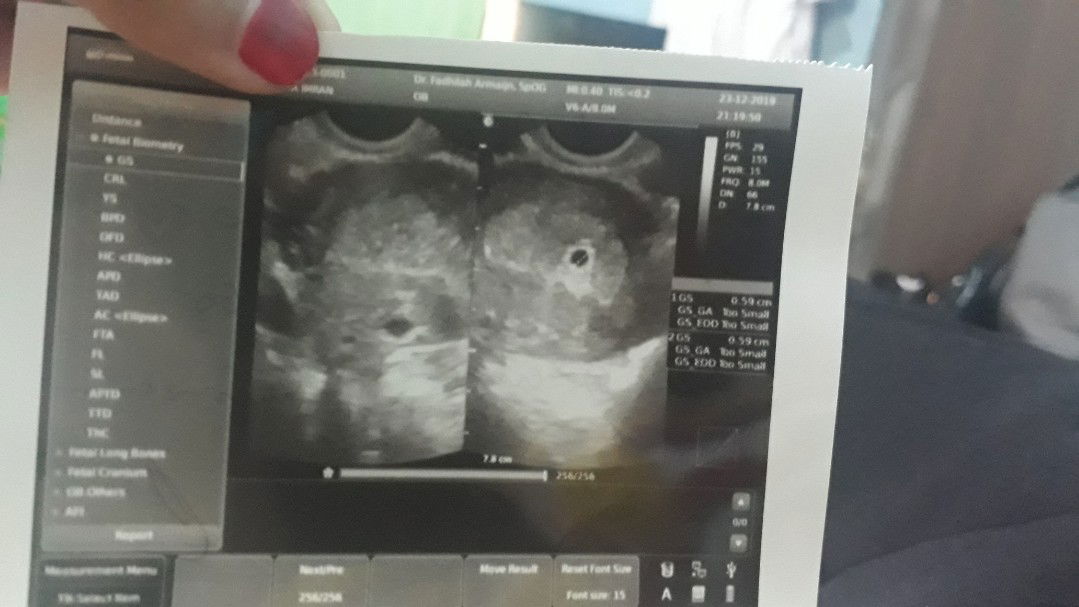

Pngn share pnglmn aku saat hamil... Jd aku haid trkhr kluarnya tgl 30 oktober, stlh itu aku hrsnya haid tgl 2 atau tgl 5 desember klu gk slh hitung,tp aku telat smpe tgl 7 gk haid akhrnya aku iseng2 TP dan Alhamdulillah aku positif... Dan di hri yg sama juga aku lngsng ke doktr, kata doktrnya ada penebalan dinding rahim. Aku di suru blk lgi 2 mnggu kemudian... brarti tgl 21 aku hrs cekup lg, tp di tgl 21 aku lg ad acara makanya aku sma suami majuin tgl 20 kita ke doktr... di saat itu memurut doktr usia kandungn aku udh 7 mnggu dan pas di USG blm kelihatan janin sama kantongnya dan akhrnya doktr memutuskn transvagina nah kliahatanlah kantongnya tp blm kelihatan janin. Aku syok dong soalnya aku kan suka cri tau tntng seputar kehamilan yg aku bc usia kandungn 7 mnggu tu biasanya udh ada janinnya tp knp aku blm ada aku udh down dong , di tmba lg doktrnya blg 2 mnggu lg aku hrs blk untk kntrl klu pas blk kntong aku blm ada janinnya brarti hrs di kurek ???... Dan gk tau apa penyebabnya tgl 22 mlm aku kluar flek wrn pink dikit bngt gk bnyk tp dy brkelanjutan smpe tgl 23 mlm.... aku sma suami akhrnya memutuskn kita ke doktr lg untk cri tau knp aku bsa kluar flek, tp di doktr yg berbeda bkn di doktr yg prtma... dan s.mlm pas USG aku sama suami bnr2 kaget krn di dlm USG aku punya 2 kantong kehamilan, yg 1 di dlm kandungn dan yg 1 nya di luar kandungan... yg di dlm kandungn usia nya bru 4 mnggu sdngkn yg di luar usianya udh 7 mnggu lebih... aku bnr2 kgt kok bisa ada 2 kntong kehamilan. Dan trnyta kantong yg di liat doktr kndungn yg prtma aku itu adlh kantong yg di luar kandungn. Ada 2 opsi klu bkn kantong kehamilan brarti kista... tp setau aku org yg pu.a kista itu ciri2a suka haid gk lncr sama klu haid skt bngt prutnya... Alhamdulillah aku dr awl haid smpe sblm mnkh gk prn telat haid dan klu haid sktnya biasa aja, jd gk mngkn kista krn aku hmil skrng juga krn aku sma suami program, klu program kan transvagina tp hrsnya klu ad kista udh ketahuan dr awal program tp kndungn aku bersih dan bagus... knp skrng bisa ada kista... ini kehamilan prtma aku dan usian prnkhn aku sma suami bru 7bln. Jd mnurut aku bkn kista itu mmng kntong kehamilan... dan sprti biasa aku di mnta blk lgi 2 mnggu kemudian bru bsa di liat apa kah itu kista atau kantong kehamilan... stlh itu bru bsa di cri solusinya mau di apain... krn Alhamdulillah bngt kantong kehamilan aku yg bru 4 mnggu itu posisinya bnr2 bgs dan kntongya juga masih sngt bgt... tp tktnya kntong yg di luar kandungn itu bisa berpengaru sma kantong yg bru jadi... Jd skrng aku sma suami lg dek2an bngt menunggu 2 mnggu lg... smg semuanya baik2 saja Amiiiiin Allahuma Amiiiin (ini foto hasil USG aku yg prtma,kedua dan ke tiga)